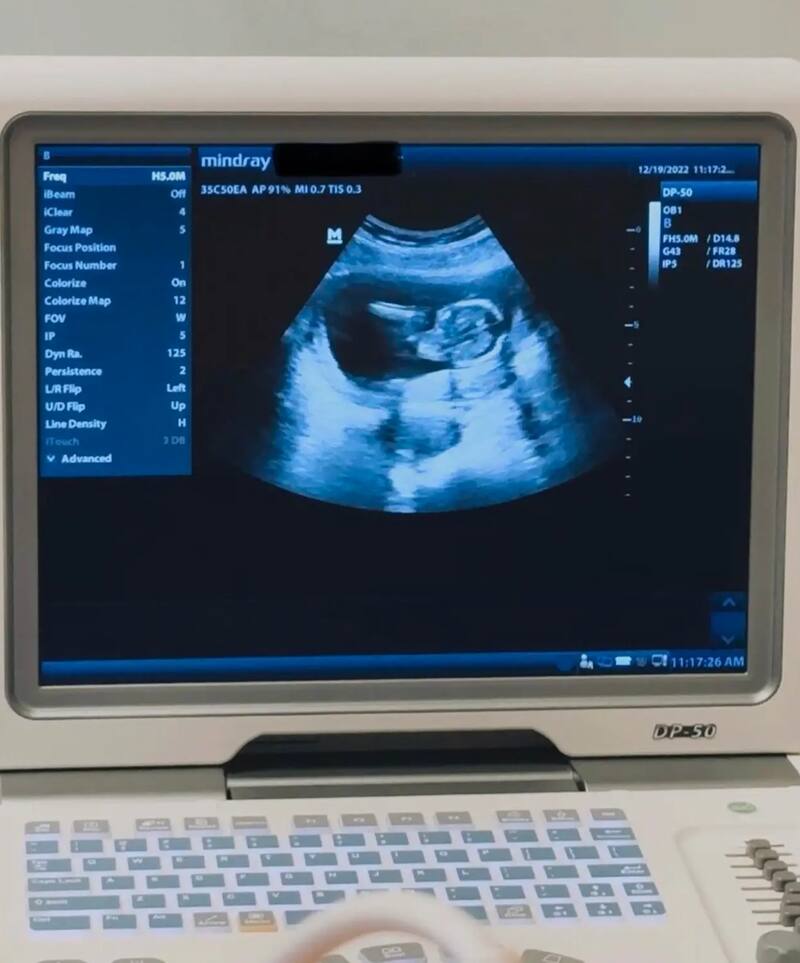

Baldwin de 27 años dio la noticia a través de su Instagram este fin de semana, publicando una foto de un ultrasonido junto con la leyenda "Feliz año nuevo".